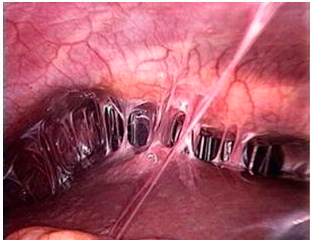

3. Surgical management (if tube has ruptured)

a. Laparoscopic salpingectomy

b. Laparoscopic salpingotomy

Salpingectomy is the surgical removal of a fallopian tube.

Salpingostomy (also called neosalpingostomy) is the creation of an opening into the fallopian tube, but the tube itself is not removed in this procedure.15